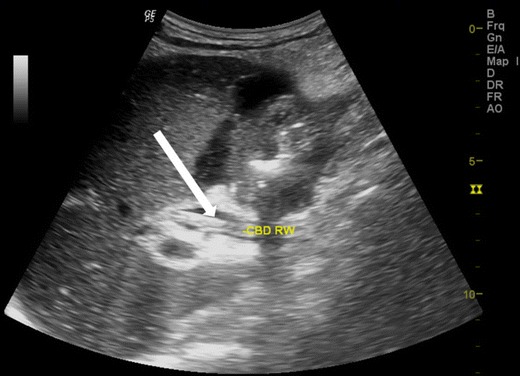

The worm in the CBD can be seen as single or multiple tubular, linear echogenic non-shadowing walls (strip sign) (Fig. 2). On rare occasions, too many worms inside the CBD can appear as multiple echogenic non-shadowing linear interfaces, giving a classical spaghetti sign (Fig. 3a ,b and c). CBD round worms sometimes has a pseudotumour appearance (Fig. 4). CBD and intrahepatic ducts can become very dilated; however, obstructive jaundice is exceedingly rare.

Fig. 2.

A patient with acute epigastrium, CBD showing double linear echogenic wall indicating ascariasis”strip sign” (white arrow)

Fig. 3.

A 14-year-old female with acute biliary colic. (a) Multiple ascaris in CBD, the spaghetti sign, CBD is filled with multiple worms (long thick white arrow), (b) intra hepatic duct of the left lobe of liver showing a double linear echogenic wall indicating ascariasis (white arrow) and (c) following antihelminthic medication, sonography was repeated the next day showing reduction in the number of worms. Note double echogenic walls (strip sign) of CBD round worm (white arrow)

Fig. 4.

A 35-year-old male with acute abdomen showing pseudotumour-like shadows in the CBD (thick white arrow). Note that the spaghetti sign is seen in the long section (thin white arrow)